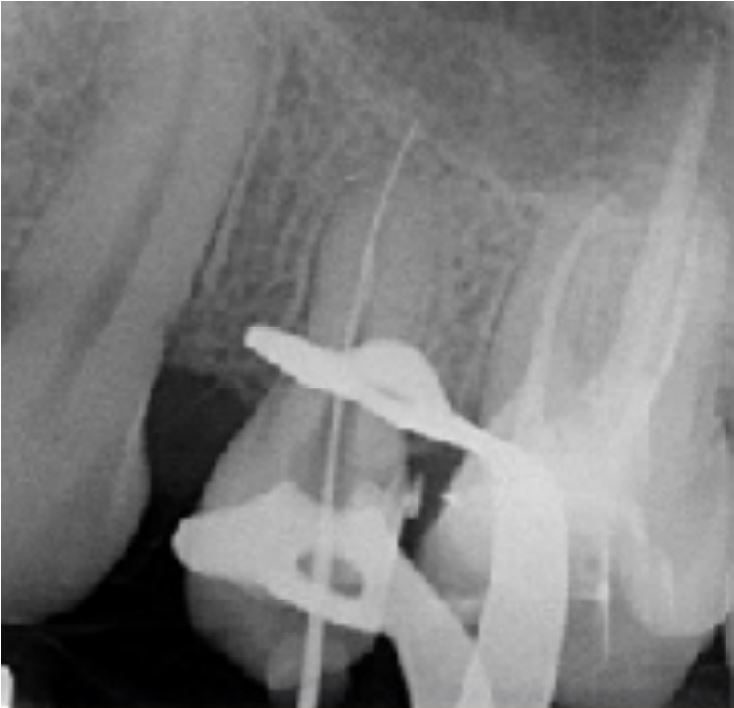

Sequenza operatoria

- Lunghezza di lavoro determinata con lima manuale K10

- Sistema canalare sagomato con la sequenza FANTA ROTARY fino all'ultima lima 30/04%

- Lima apicale maestra di 30/100

- Otturazione con guttaperca e cemento all'ossido di zinco-eugenolo

- Termocompattazione